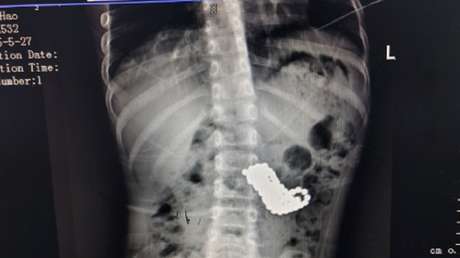

Sin embargo, después de cinco o seis días los padres del chico notaron que la bolita magnética no había sido expulsada, por los que decidieron llevarlo al Hospital Afiliado de la Universidad de Medicina de Guizhou, en donde después de que se le tomara una radiografía se descubrió que realmente había comido una gran cantidad de cuentas.

Según informa el hospital, tras más de cuatro horas de cirugía, en las que fue utilizado equipo especializado de gastroscopía, los médicos pudieron recuperar del estómago del menor las 123 cuentas de 0,5 centímetros que había ingerido.